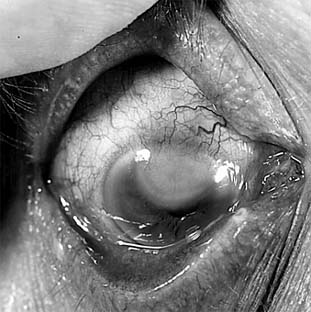

Pneumococcal corneal ulcer usually occurs 24-48 hours after inoculation of an abraded cornea. It typically produces a gray, fairly well circumscribed ulcer that tends to spread erratically from the original site of infection toward the center of the cornea (Figure 6-1). The advancing border shows active ulceration and infiltration as the trailing border begins to heal. (This creeping effect suggested the term "acute serpiginous ulcer.") The superficial corneal layers become involved first and then the deep parenchyma. The cornea surrounding the ulcer is often clear. Hypopyon is common. Scrapings from the leading edge of a pneumococcal corneal ulcer usually contain gram-positive lancet-shaped diplococci. Drugs recommended for use in treatment are listed in Tables 6-2 and 6-3. Concurrent dacryocystitis should also be treated.

Figure 6-1

Figure 6-1: Pneumococcal corneal ulcer with hypopyon.